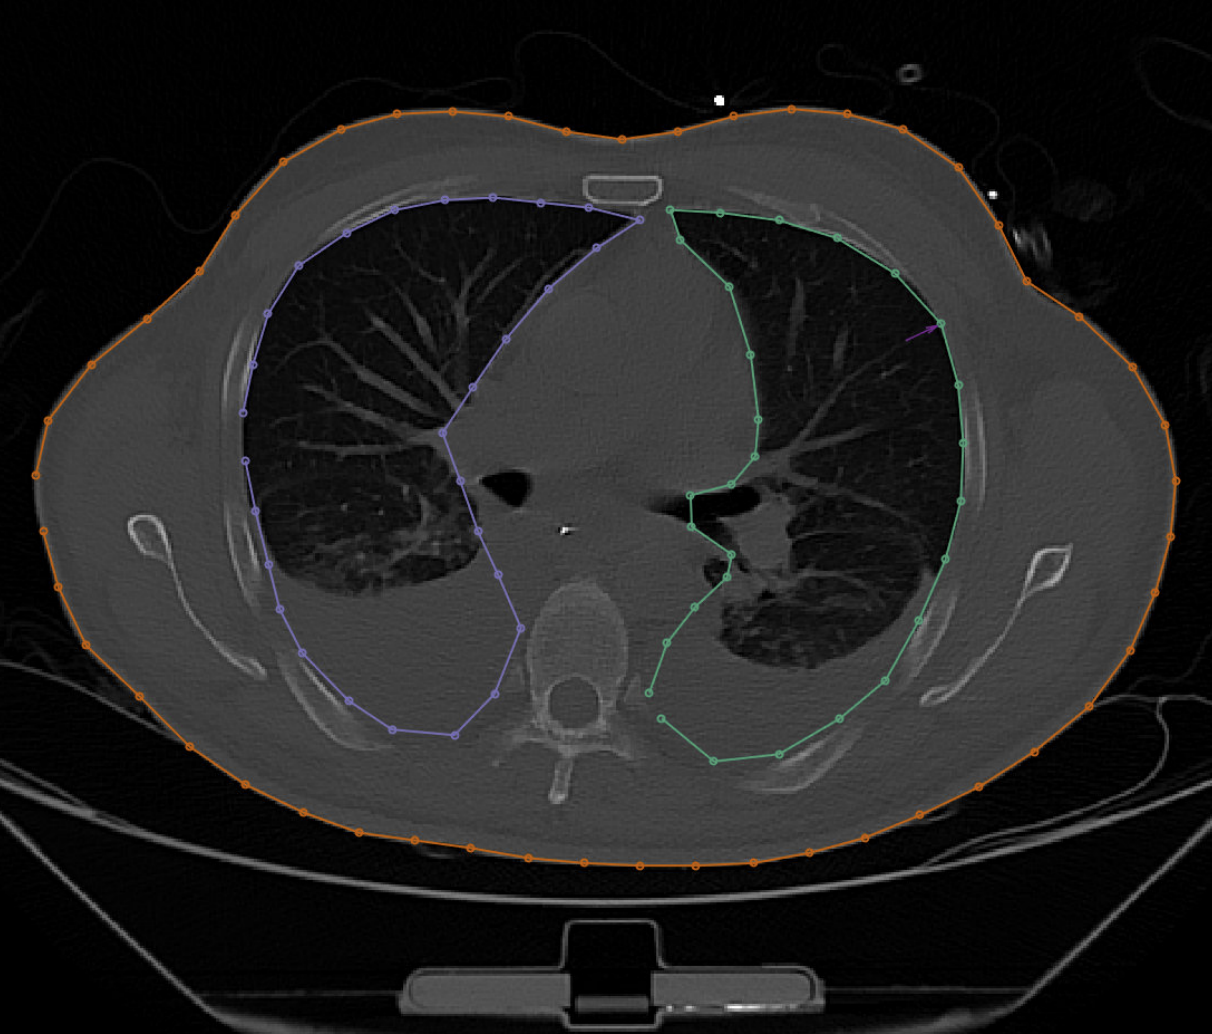

Segmentation Tool

Lung segmentation tool

Automatically segmenting lungs and presenting clinicians with an interface for correction